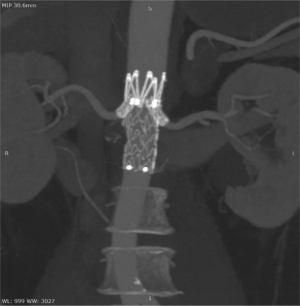

Под местной анестезией выполнено четыре пункции сосудов рук и ног (плечевые и бедренные артерии справа и слева) и выполнено уникальное эндоваскулярное протезирование брюшного отдела аорты стент-графтом от уровня почечных артерий и самих почечных артерий, таким образом исключив из кровотока патологический процесс – артериовенозное сообщение.

По данным контрольной ангиографии непосредственно после оперативного вмешательства: адекватное позиционирование стент-графтов, без признаков диссекций, нарушения целостности артериальных сосудов. Почечные артерии и верхняя брыжеечная артерия проходимы, почечная вена визуально уменьшилась до нормальных размеров.